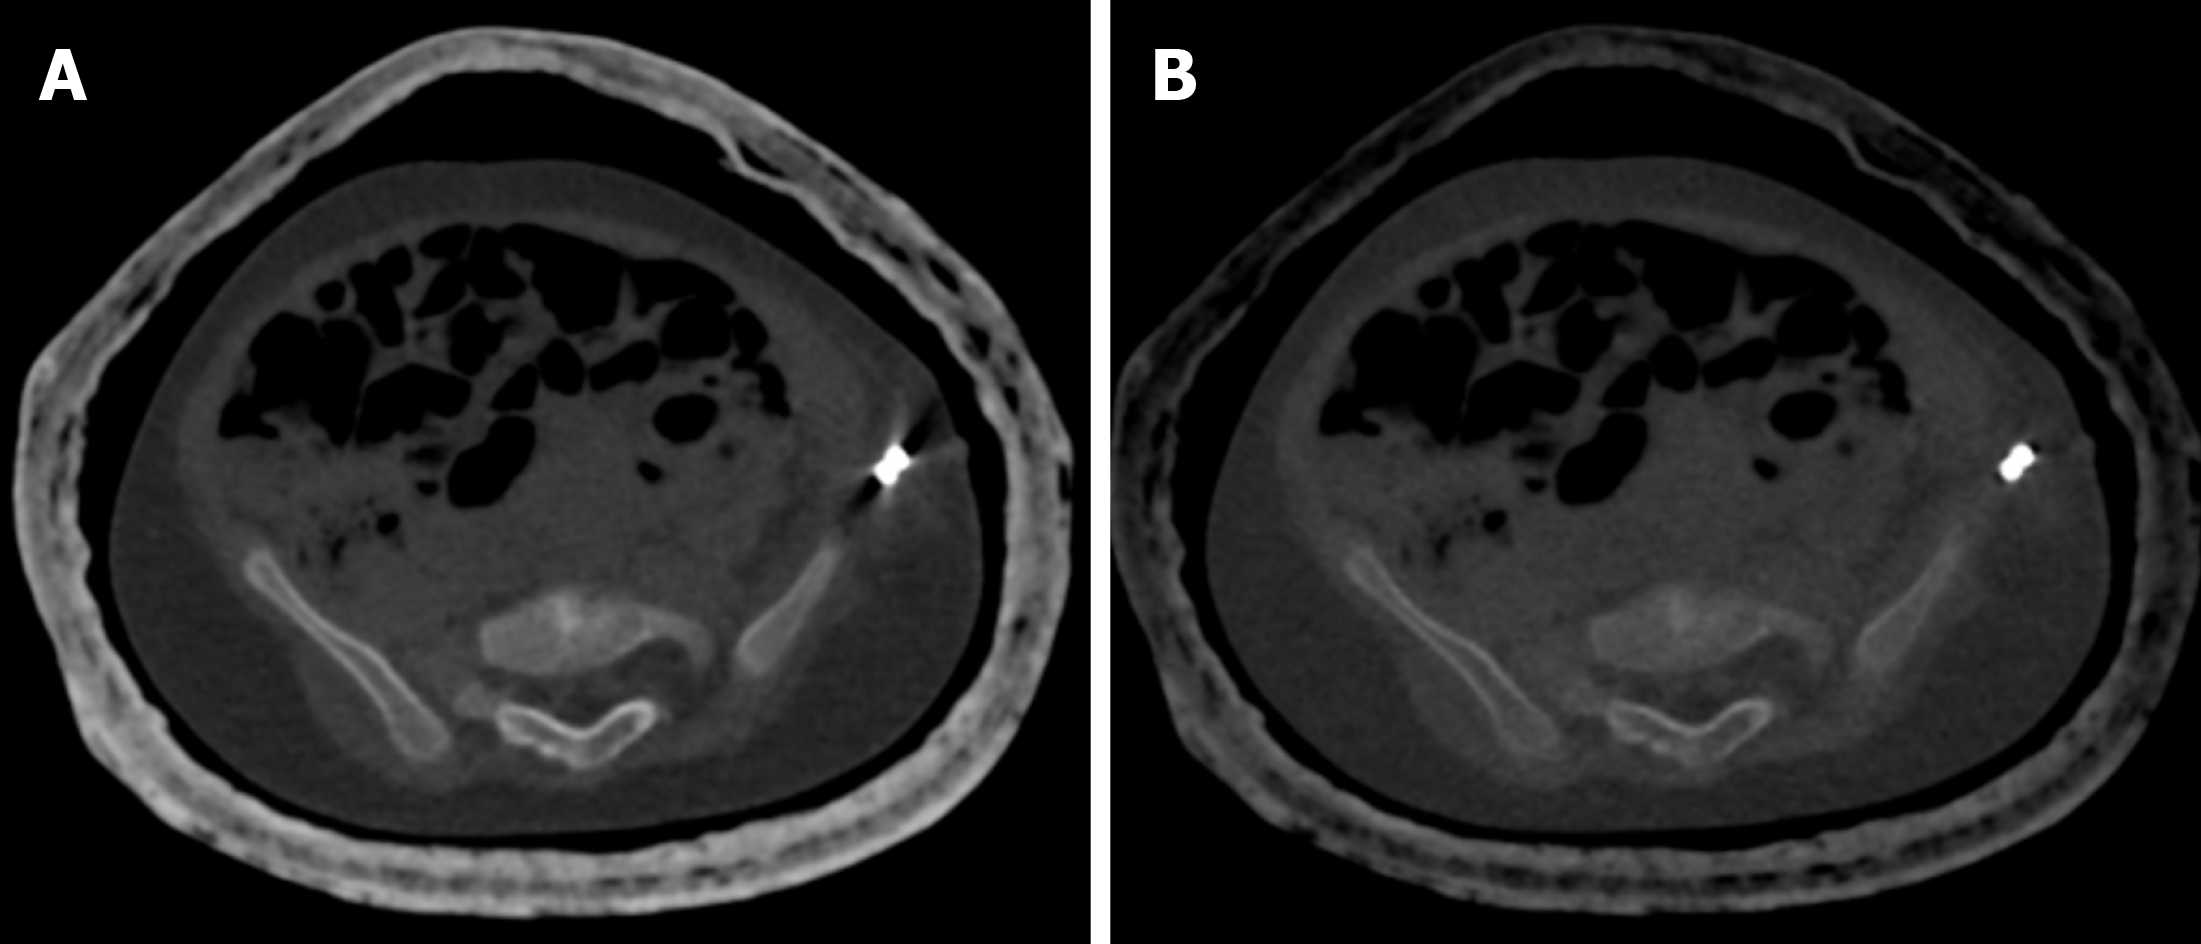

Figure 13 A 2-year-old female who underwent CT of the bilateral hip joints after salter osteotomy for developmental dysplasia of the hip to look for the status of the femur head and acetabulum.

A: Axial bone window image at 70 kV showed marked streak artifacts due to the K-wire inserted along the left iliac bone; B: Axial bone window image at 150 kV showed almost no streak artifacts.